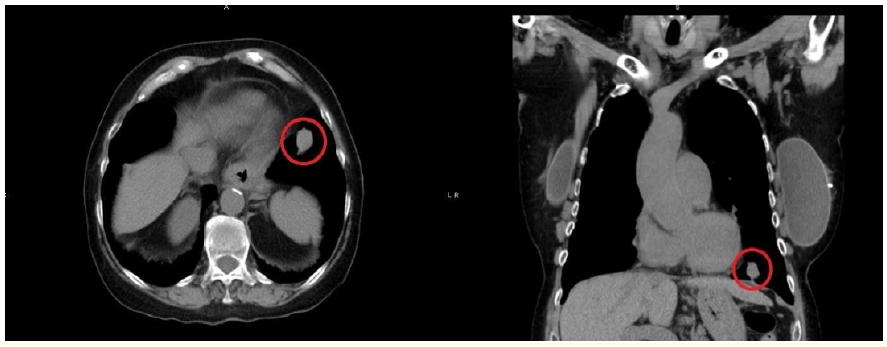

Chest X-Ray Delayed Diagnosis of Lung Cancer with Liver Metastases: Case Report of Misinterpreted Bronchopneumonia

Petar Avramovski, Marija Georgievska, Stefan Talev, Maja Avramovska, Vesna Siklovska, Biljana Ilkovska, Julijana Petrovska and Dejan Zdraveski. 6(2): 01-07.